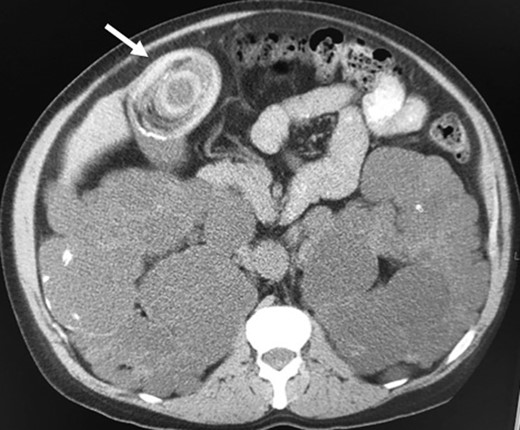

The patient presented to the ER complaining of abdominal pain, vomiting, and one abundant bloody diarrhea. His abdomen was distended with diffuse tenderness on physical examination. His vital signs were unremarkable except for a heart rate at 115/min. An abdominopelvic CT scan was performed, and showed a CCF with the giant 5 × 7 cm2 gallstone in the proximal transverse colon (Fig. 2). Oral contrast did not reveal any cholecystoduodenal communication. Blood tests revealed the following: white blood count 11.8 × 109/L, hemoglobin 145 g/L, creatinine 786 μmol/L, international normalized ratio (INR) 2.71 and normal alanine transaminase, aspartate transaminase, bilirubin, alkaline phosphatase and lipase.

Giant gallstone located in the proximal transverse colon on abdominopelvic CT scan.